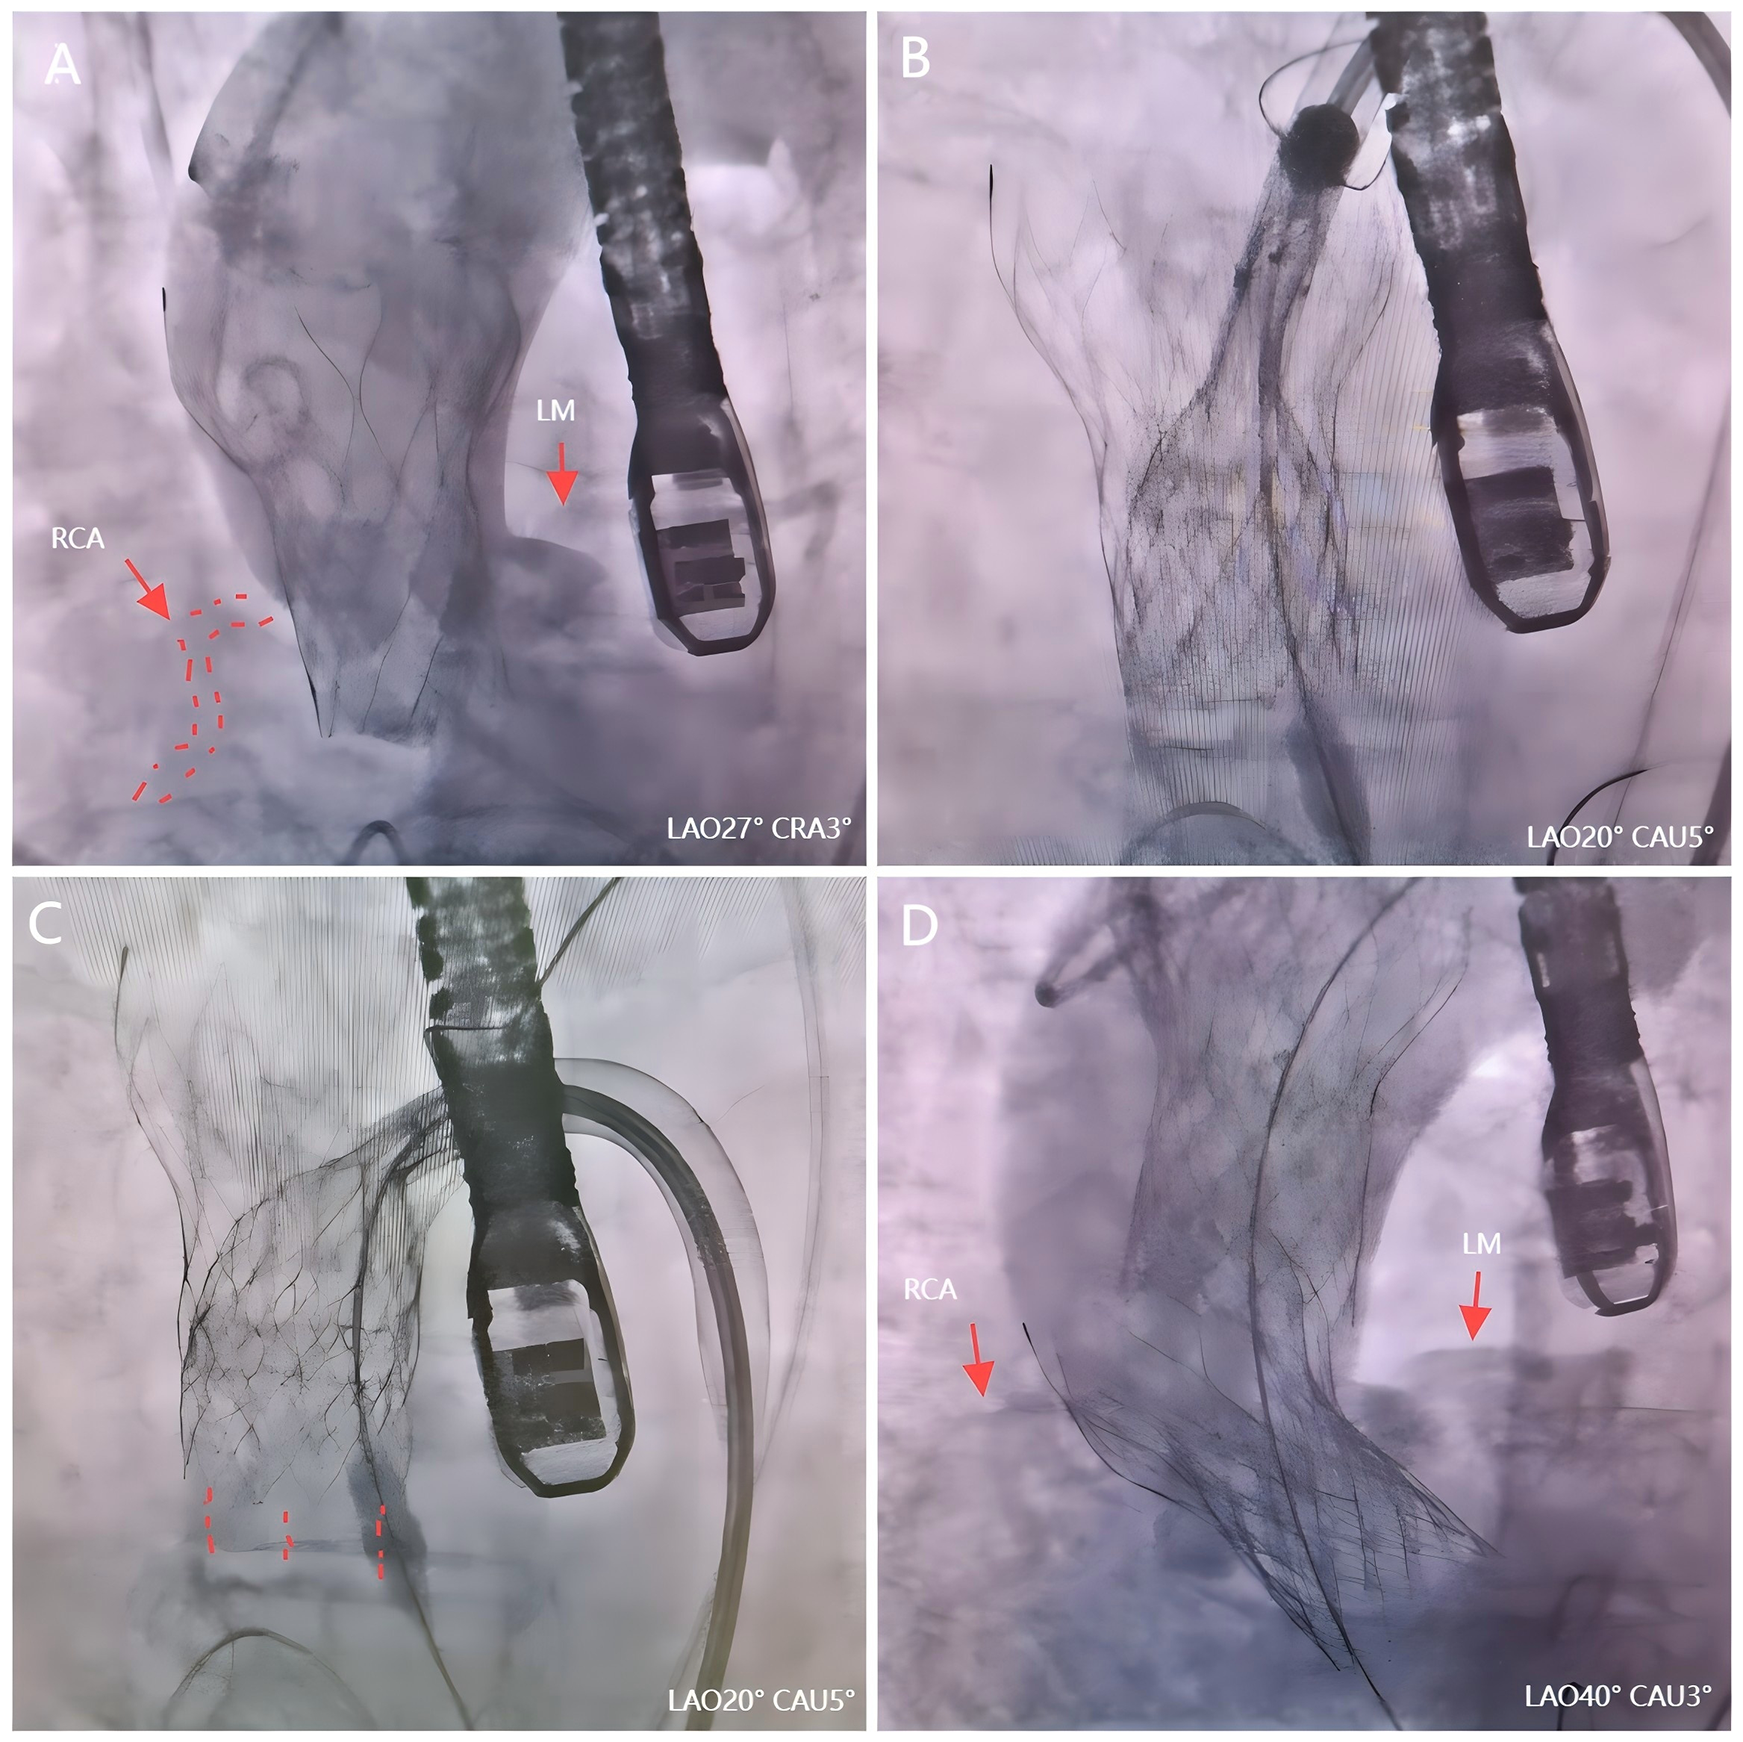

Figure 2

The second valve drag technique during TAVR. (A) Angiography revealed an acute obstruction of the right coronary artery. (B) The second valve successfully captured the first dislocated valve. (C) The first valve was repositioned by pulling the second valve toward the aorta arch. (D) Valve-valve intervention effectively addressed AS.

We firstly used one Snare from the left femoral artery to pull the valve but it failed because it caused different axis between the valve and ascending aorta. Then we tried to use the second Snare from the right radial artery to change coaxiality but it could not catch the valve stent in a short time. Several minutes after use of the second Snare, the ECG monitors showed obvious elevation of ST segment and the hemodynamics became unstable (blood pressure felled to 40/20 mmHg). Thus, we quickly switched to the second valve drag technique. A second 23 mm Taurus self-expanding valve was promptly prepared within 3 min following this severe complication. With the aid of a snare, it successfully captured the first dislocated valve by leveraging its maximum expansion capacity (Figure 2B). Then we used the second valve and its delivery system to pull up the first valve through pull the second valve toward the aorta arch (Figure 2C). Ultimately, the initial dislocated valve was safely dragged into the ascending aorta, resulting in restoration of RCA in just 7 min. The patient's circulation had also been stabilized. Subsequently, successful valve-valve intervention effectively addressed AS and paravalvular leakage (Figure 2D). During the observation period, no aortic dissection or mitral valve dysfunction were detected, with an average pressure gradient of 14 mmHg and a velocity of 1.8 m/s. Subsequently, the patient received post-TAVR treatment in the cardiac care unit (CCU).